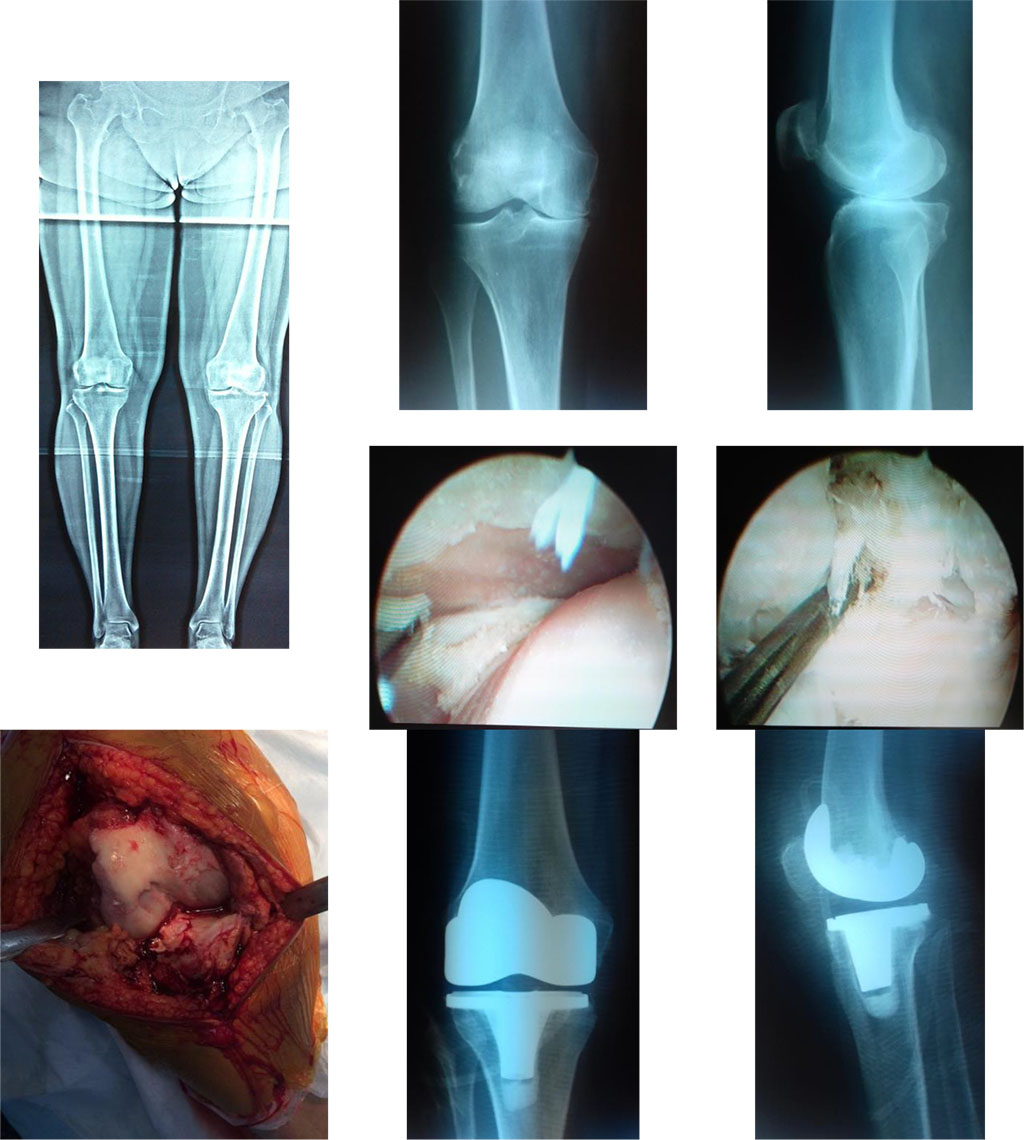

The patients with good results had mostly had 3rd stage deforming arthritis with their range of motion restricted insignificantly (from 5º to 20°), with the joint deformity absent or expressed slightly (varus or valgus, 10–15°), and 1-2 stage of knee instability (Fig.3).

Figure 3. X-ray images before and after total knee arthroplasty. An intraoperative image (the defect of the medial femoral condyle).

Diagnosis: bilateral gonarthrosis, 2-3 stage, with a right knee varus deformity; flexion contracture of the right knee - 15˚.

The patient complains of constant pain in her right knee feeling ill over three years. During the recent 4-5 months, she started to notice the worsening of her conditions. The patient had undergone total arthroplasty of her right knee. Twelve months later, she claimed for slight periodical pain after a durable physical load; the range of motion of the knee is full. The result was good (KSS – 84).

A satisfactory result of total knee arthroplasty is mostly associated with a restricted range of motions of the knee. Before the surgery: diagnosed the 4th stage of the disease with flexion and extension contractures, expressed varus deformity of a knee (over 20°), and instability of the capsular-ligament system. The pain syndrome in the area of a patella-femoral articulation and the popliteal fossae cased the restriction of the motions in the knee after total knee arthroplasty. Besides, most patients fail to complete a full rehabilitation course, and it impairs functional recovery of the joint and the extremity as a whole.